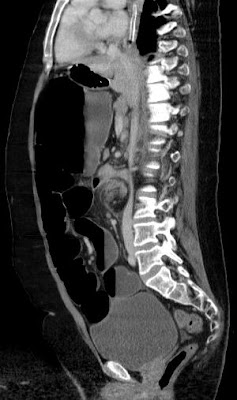

Coronal reformatted CT: dilated cecum  in the left upper quadrant of the abdomen. The cecum is displacing the stomach superiorly. Obstructed small bowel.

whirl-sign according to the twisted cecum (organoaxial form)